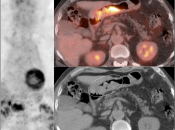

• The utility of PET/CT lies in its assessment of regional nodes and distant metastatic disease.

• Distant Disease: Most commonly to the liver, peritoneum, lung and bone.

The difficulty with PET/CT imaging and gastric cancer is that it is both easy to overlook and easy to over-call.

Normal FDG uptake involving the stomach can be extremely variable. It is not uncommon to see diffuse intense uptake throughout the entire stomach or intense uptake limited to only a segment of the stomach (fundus, body or antrum).

In general, we raise a suspicion of gastric malignancy if:

• Focal or regional hypermetabolic activity is accompanied by at least the suggestion of associated wall thickening (often difficult to assess if the patient’s stomach is suboptimally distended with water or oral contrast);

• Uptake is extremely focal (more likely to represent malignancy or ulcer);

• Focal/segmental uptake is extremely intense.

• Obviously, signs of associated metastatic disease on the scan give the radiologist much greater confidence in reporting a suspected primary gastric lesion.